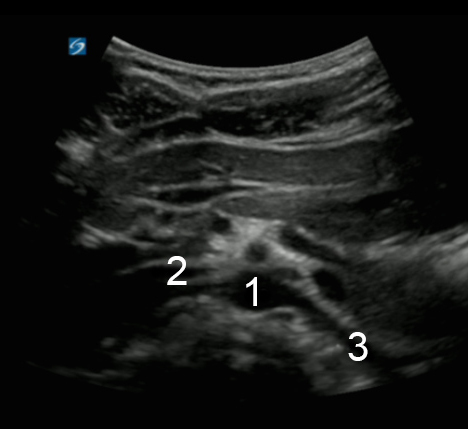

Bild: Aorta, Arteria mesenterica superior (AMS), Arteria renalis

1. Aorta (Ao)

2. Rechte Arteria renalis (RAR)

3. Linke Arteria renalis (LAR)